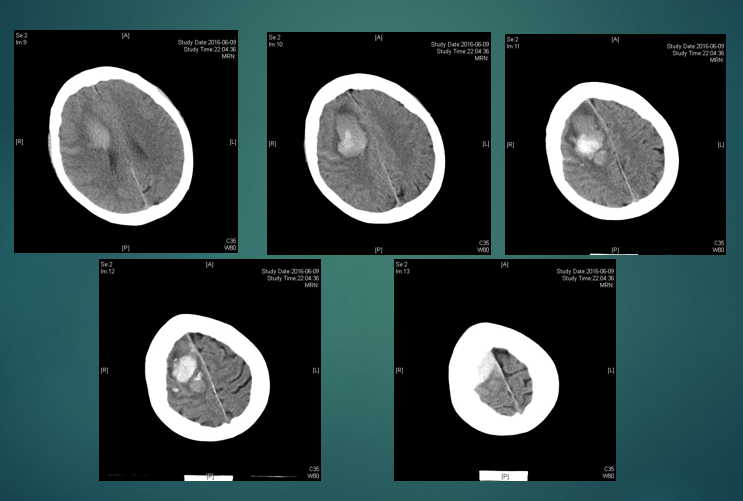

入住神经外科。CT示出血量约150 ml。

2021.04.23(发病第1天)CT